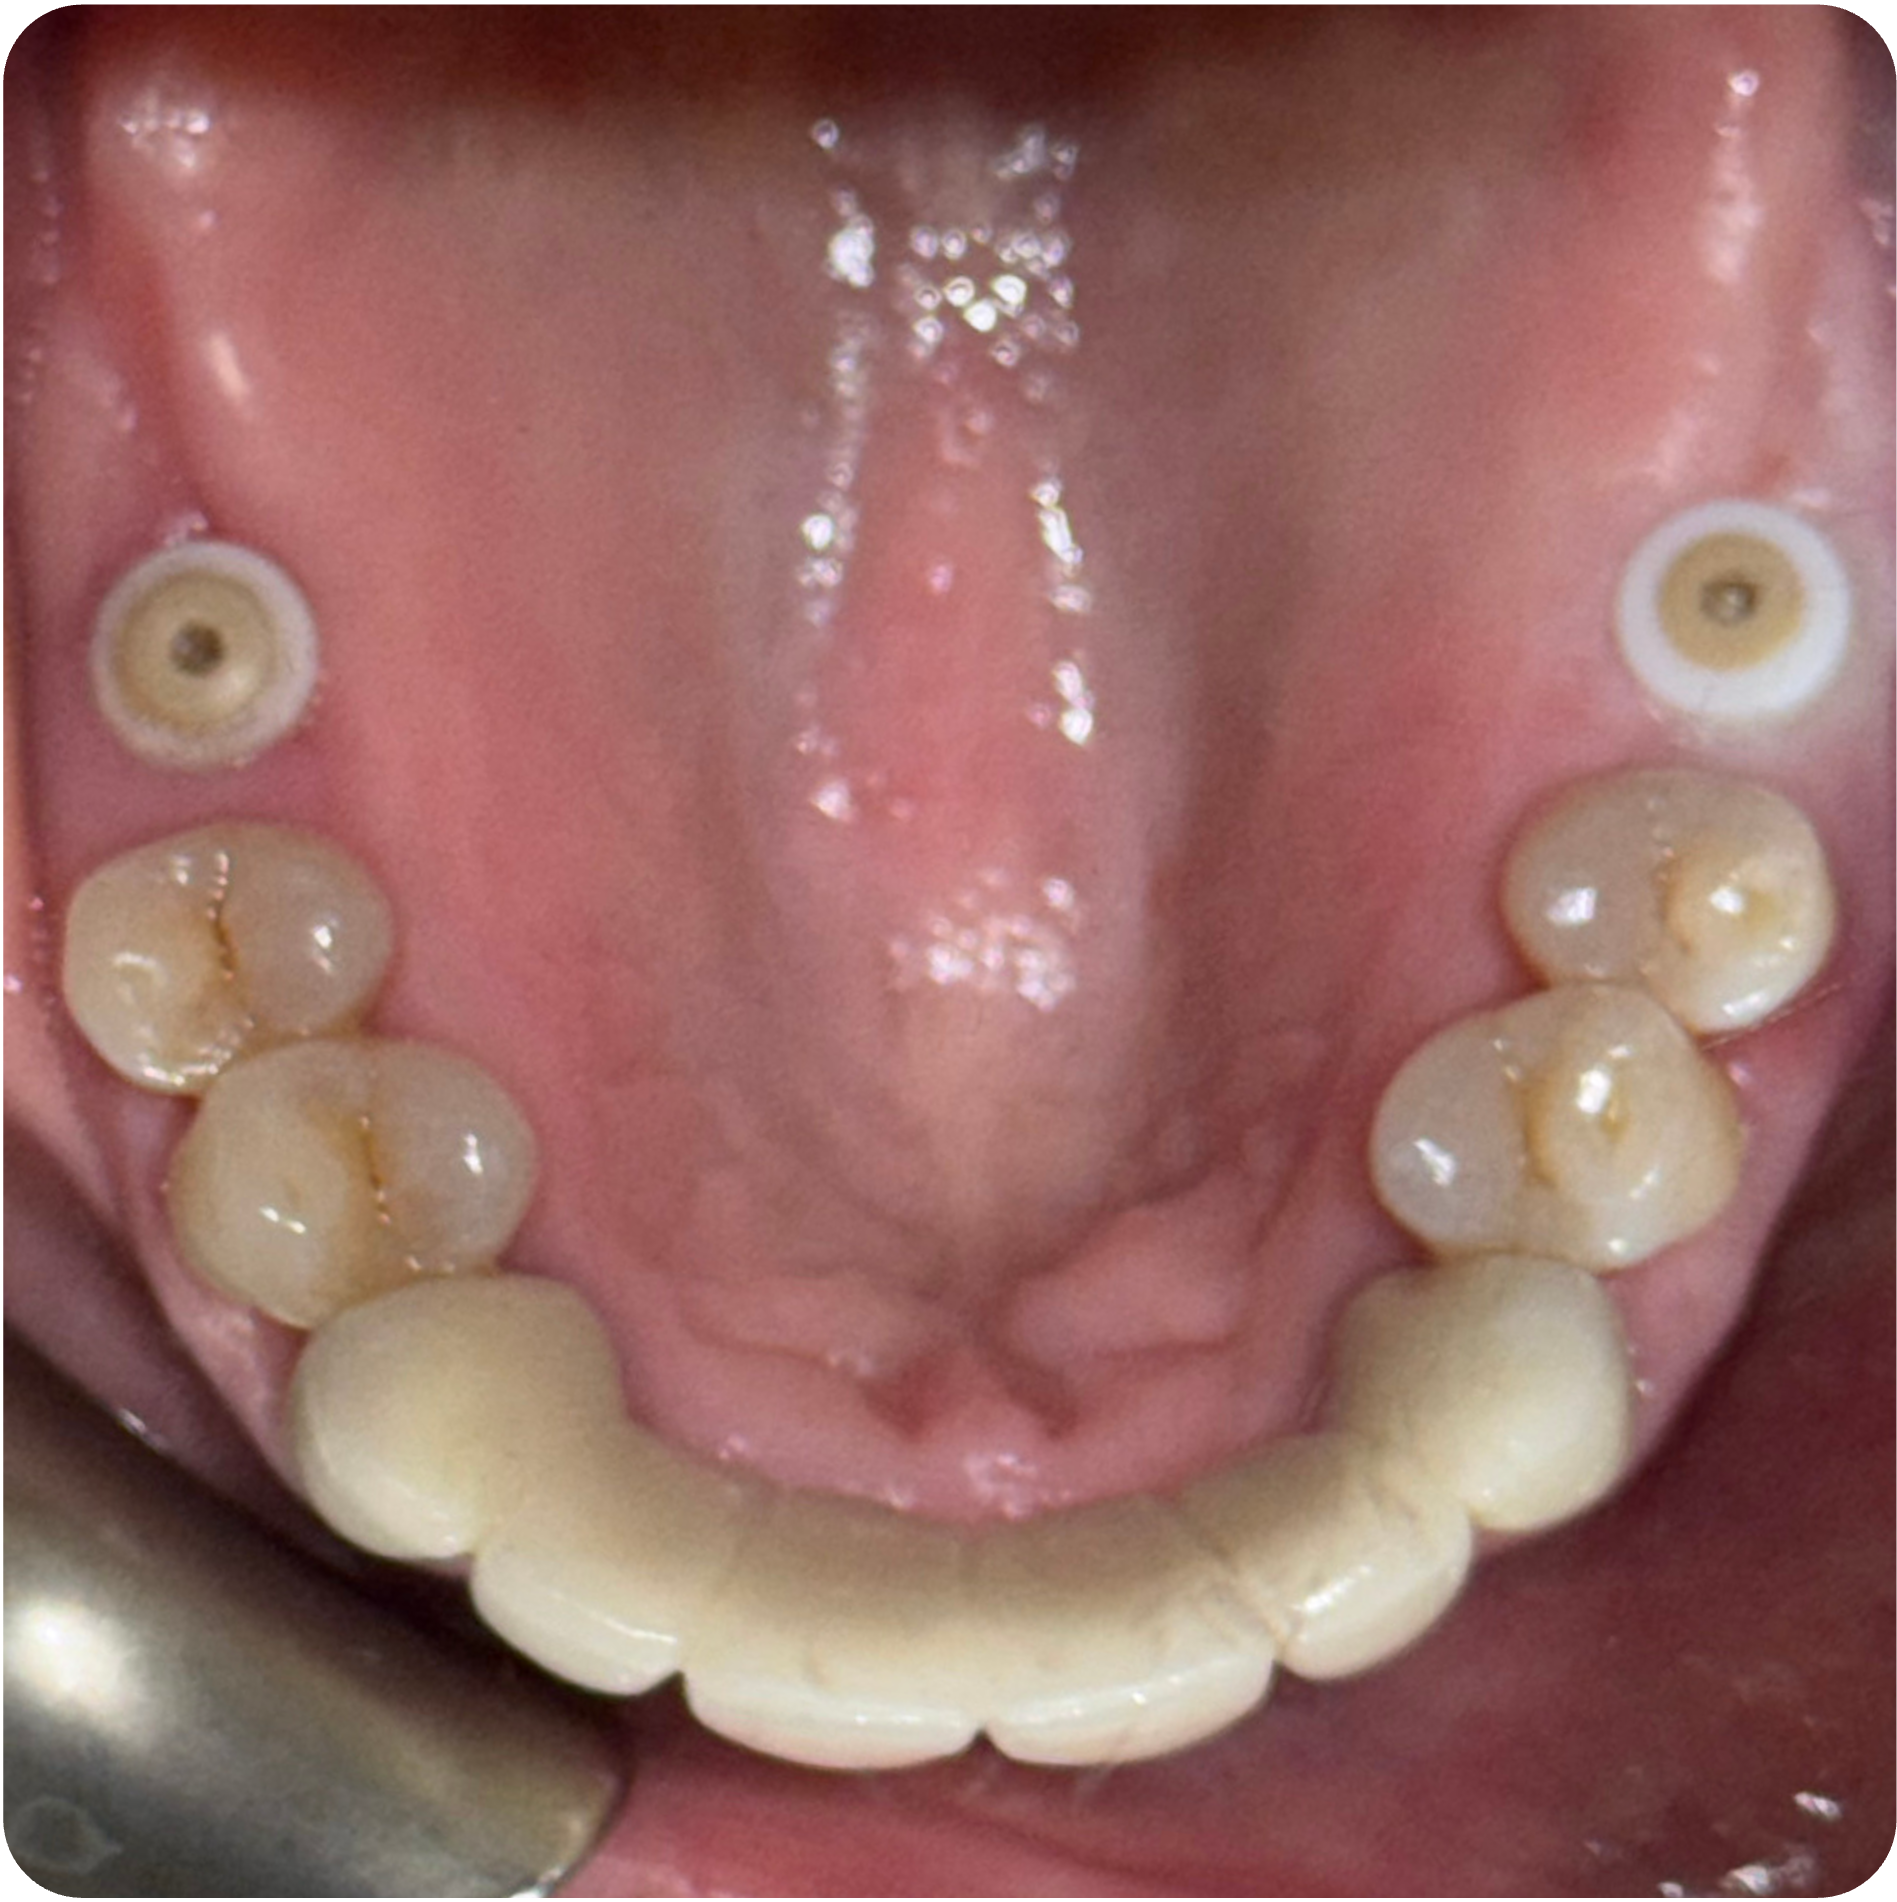

November 26, 2025Implant placement (#3 and #30).

December 02, 2025Implant placement (#14 and #19).

Visual Case Progression

All clinical images are shown at a consistent size for easy comparison.

- Implant Placement in Stabilized Sites: Once infection was controlled and bone matured, implants were placed in #3, #30, #14, and #19 to restore function and long-term structural integrity.